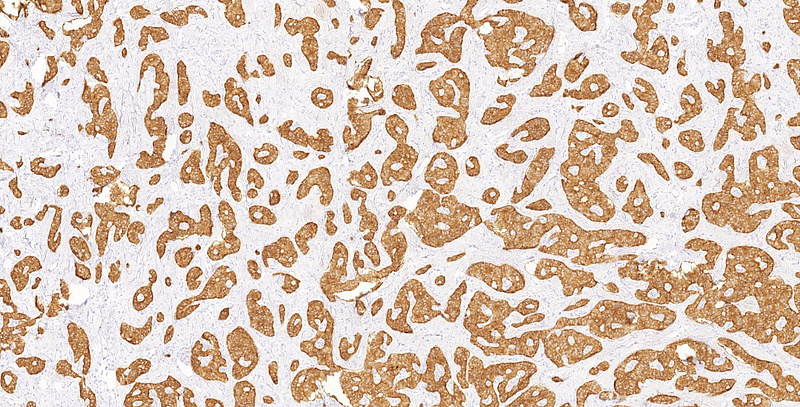

On low power, we noted a nest-forming, occasionally rosettoid tumor with expansive border (Panel A). The tumor cells were monomorphic with ample, eosinophilic cytoplasm, salt-and-pepper chromatin and occasional inconspicuous nucleoli. Mitoses were not observed. No necrosis. The stroma of the tumor consisted of exuberant, dense, hyalinic collagen with central calcification (Panel B). No lymphovascular or perineural invasion was identified. Immunohistochemistry revealed a diffuse cytoplasmic positivity for synaptophysin (Panel C), perinuclear dotlike positivity for chromogranin-A (Panel D) and diffuse cytoplasmic positivity for Insulin (Panel E). The Ki-67 labelling index was less than 1% (Panel F).